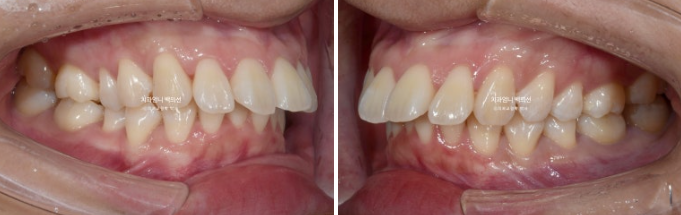

정면을 보시면 윗니가 아랫니를 많이 덮고 있습니다.

아랫니가 거의 보이지 않습니다.

이런 부정교합을 과개교합 이라고 합니다.

윗니도 많이 뻗쳐 있습니다.

배열도 좋지 않아서 발치교정 권유드렸습니다.

위 작은어금니 2개 발치 아래는 매복사랑니 발치 후 작은 어금니 발치 없이 미니스크류를 심고 후방이동 하는 계획입니다.

교정장치는 인비절라인이며 23년 3월에 장치를 끼기 시작했습니다.

과개교합은 잘 개선이 되었습니다.

발치공간이 아직 남아있고 앞니 각도의 개선이 더 필요합니다.

개선된 과개교합과 일치된 중심선

앞니 뻗침도 많이 좋아졌습니다.